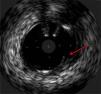

The procedure was performed by radial approach using a 7F guiding catheter. Plaque preparation was performed with rotational atherectomy using a 1.5 mm burr (Figure 3) and further predilation with a cutting balloon (3-3.5 mm). After balloon dilatation, rupture of severely calcified plaque was detected by IVUS (Eagle Eye; Volcano Corporation, Rancho Cordova, CA, USA), so we proceeded to implant a 3.5 mm×20 mm CRE 8 DES in the LM and LAD (Figures 4 and 5). At this point the wire was accidentally pulled back and was reintroduced into the LM and LAD. Post-dilatation was performed with a 4 mm non-compliant balloon. IVUS examination with manual pull-back at this stage revealed that the proximal part of the stent in the LM had been crushed as a result of lateral reintroduction of the wire through a proximal stent strut. The patient remained stable with normal flow in the LM and LAD. Guided by IVUS, a second wire (Sion, Asahi Intecc, Japan), with a 30° bend in its 1 mm distal tip, was introduced within the crushed stent segment (Figure 6). Once the guidewire was positioned inside the stent, progressive dilations with small (1.5 mm) to large (4 mm) balloons were performed until the stent regained its cylindrical shape (Figure 7). IVUS exploration detected an image suggesting dissection in the proximal end of the stent (Figure 8), and so a second DES (4 mm×8 mm Onyx) was implanted in the ostial-proximal segment of the LM, overlapping the previous stent (Figure 9), with an adequate angiographic final result (Figures 10 and 11). IVUS revealed correct stent expansion and apposition in the LM (Figure 12).

As the patient was stable, and taking advantage of the size of the 7F guiding catheter, we introduced a new guidewire under IVUS guidance within the lumen of the crushed stent segment. After step-by-step dilatation with smaller to larger balloons, the crushed stent segment regained its cylindrical shape. Although another practical solution would have been to implant a new stent (stent-in-stent), we chose the former strategy and consequently avoided the placement of multiple layers in the proximal segment of the LM. Finally, the implantation of a second stent, overlapping with the proximal end of the previous stent in the LM, enabled the coverage of both the proximal end dissection and the proximal part of the reconstructed stent segment. Considering that in the latter part the struts appeared to be incomplete in some circumferential points (Figure 7), the implantation of a new stent could remedy this defect.